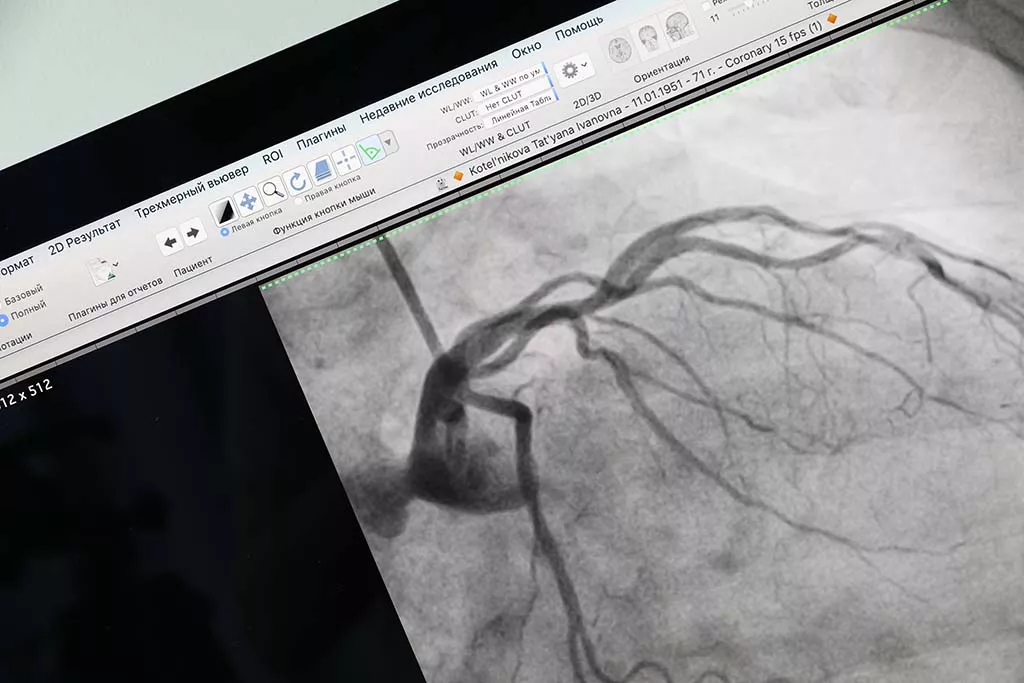

В начале операции хирург Павел Мезенцев под местной анестезией сделал проколы в подключичной и бедренной венах, а затем через них, используя специальные трубочки, под рентгеноскопическим контролем ввел электроды в полость сердца.

На первом этапе он выполнил электрофизиологическое исследование, чтобы найти анормальный очаг, который и запускает аритмию. Для этого проводятся специальные тесты, провоцирующие нарушения ритма, а внутрисердечная кардиограмма контролируется на мониторе компьютера.

Началась операция так же, как и первая, с введения электродов в сердце. Затем повторились и другие этапы. Однако и электрофизиологическое исследование, и радиочастотная абляция проводились в условиях навигационного картирования, то есть для поиска очага аритмии была построена 3D-модель сердца, в данном случае — его левого предсердия. Такой метод позволяет более точно выполнять процедуру, а также минимизирует дозу рентгеновского облучения как пациента, так и врача.